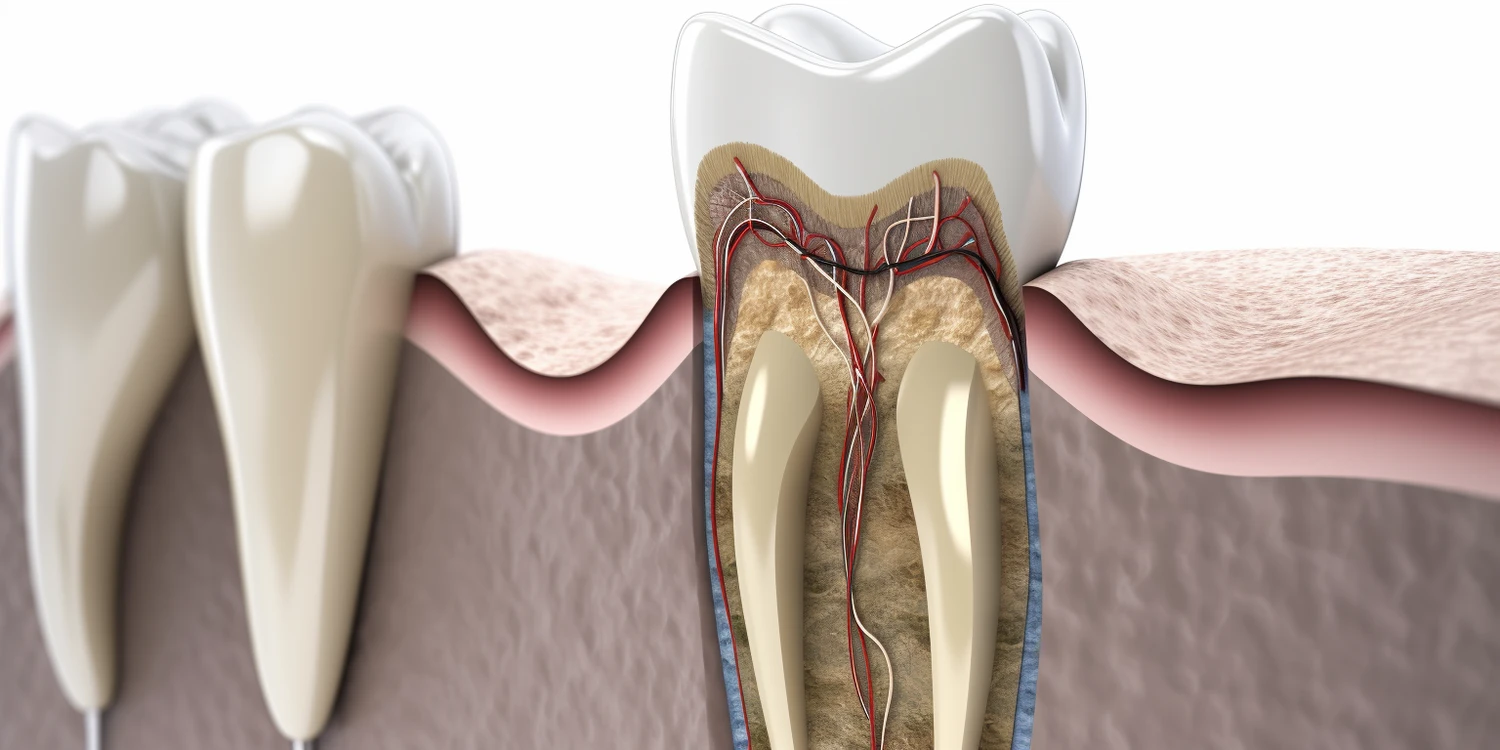

W kontekście możliwości uzyskania zwolnienia lekarskiego od dentysty istotne jest zrozumienie, jakie schorzenia stomatologiczne mogą uprawniać do takiego dokumentu. Do najczęstszych przypadków należą poważne infekcje jamy ustnej, takie jak ropień zęba czy zapalenie dziąseł, które mogą powodować silny ból oraz dyskomfort. Inne schorzenia to stany zapalne przyzębia czy problemy ze stawem skroniowo-żuchwowym, które mogą skutkować ograniczeniem ruchomości żuchwy i trudnościami w jedzeniu oraz mówieniu. W takich sytuacjach dentysta ma prawo ocenić stan zdrowia pacjenta i zdecydować o konieczności wystawienia L4. Ponadto warto wspomnieć o przypadkach wymagających interwencji chirurgicznej, takich jak usunięcie ósemek czy innych zębów wymagających zabiegów operacyjnych.